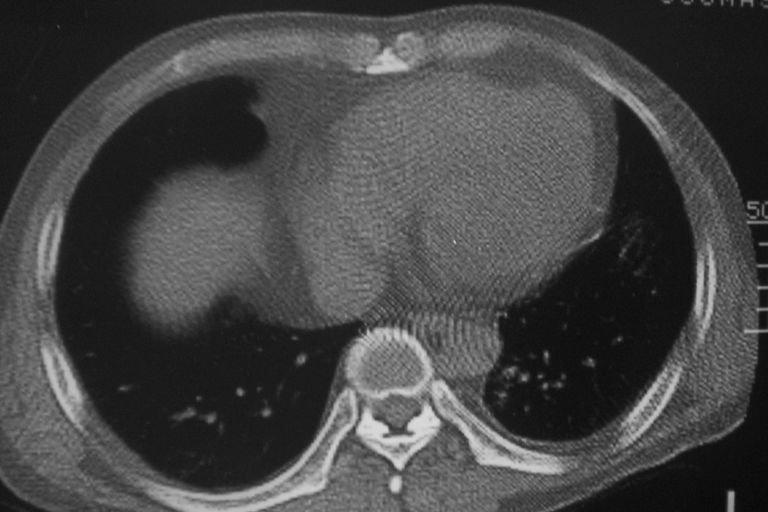

标题: CT10574:男 50岁胸部CT请会诊!

患者 男 50岁 无痛性咯血3天,无其他不适.

考虑右下肺周围型肺癌,心包积液不确切,像是脂肪

左下肺结节状软组织密度影,一个边缘有卫星病灶,邻近胸膜增厚.另一个有毛刺.心影周围水样密度影环绕.考虑:

1.肺癌可能.肺tb待排.

2.左侧胸膜增厚.心包积液.

左肺下叶多发性炎性肉芽肿性病变。